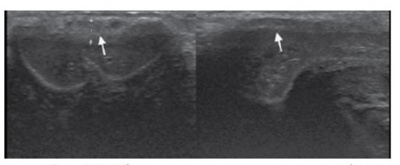

페이로니병은 음경 백막의 증식성 섬유화에 따른 것으로, 흑백모드(gray scale)로 관찰할 때 등에코성(isoechoic)으로 나타나 주변조직과 감별이 되지 않을 수 있으므로 반드시 촉진을 통해 결절을 확인하는 것이 중요하다. 부종이나 석회화가 동반되는 경우에는 고에코성(high echogenic)으로 나타나 쉽게 확인할 수 있다. 이런 석회화는 발기유발제 주사 후 칼라도플러모드를 통해 혈관의 석회화와 감별할 수 있다(그림 10).

그림 10. 페이로니병(Left: hyperechoic plaque, Right: isoechoic plaque)